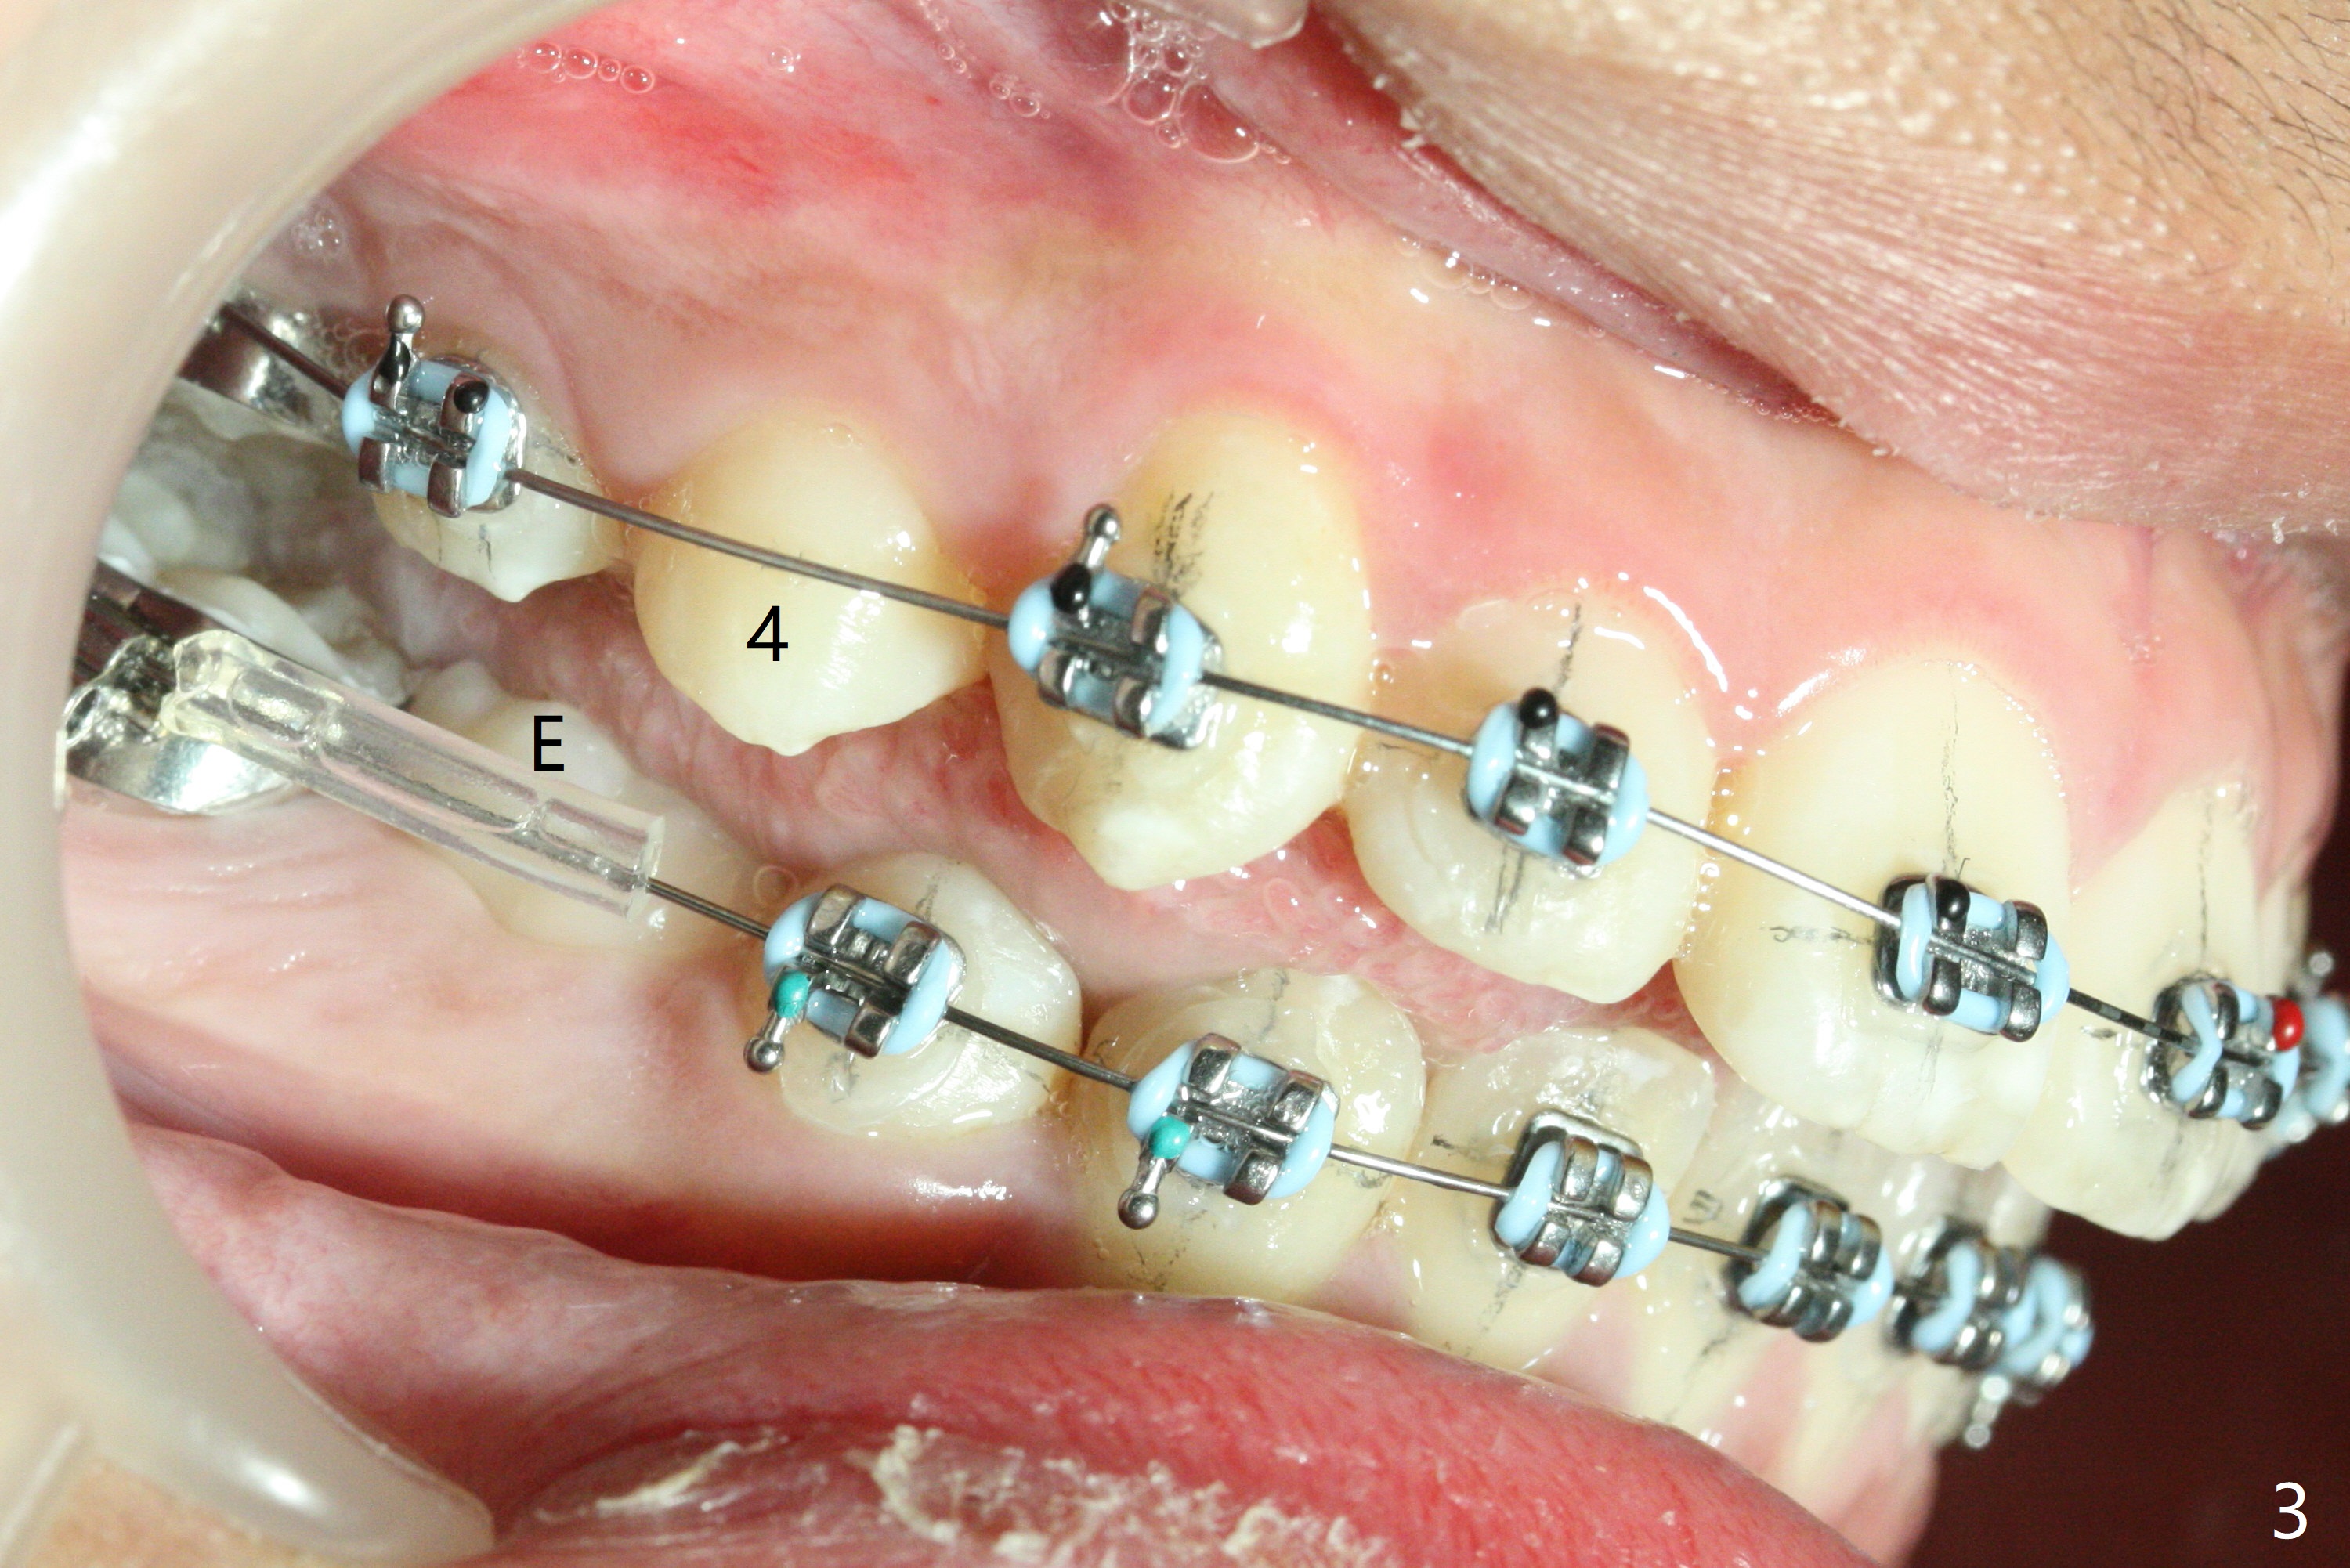

Pre-operative cephalometric X-ray shows convex facial profile (Fig.1). In fact tracing (a few days after banding) shows bimaxillary protrusion (SNA, SNB (88 and 87 degrees vs. 82, 80 (normal)). It appears that extraction orthodontics is indicated (UR4, UL5 (impacted) and LEs). The facial and upper dental midlines seem to coincide (Fig.2). No brackets or bands are placed at UR4 (because of non-cooperative (hyperactive)), LEs (Fig.3,4), or L7s (incomplete eruption, data not shown). Note wire bending between the canines and incisors, as related to correction of overbite. Shrinkable tubes are used in the region without bracket to prevent tissue injury. The upper arch seems to elongate (Fig.5, as compared to the lower one (Fig.6)). It appears that UR4 and UL5 should be extracted for normal profile and alignment. Cephalometric tracing shows that SNA and SNB are 79 and 85º, respectively, suggesting extraction (Fig.7).